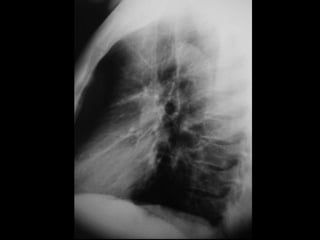

RADIOGRAFIA

• Radiografía normal

• Radiografía patológica

– Ensanchamiento mediastinal

• Técnica radiográfica

• Estructuras normales de tamaño o distribución atípica

• Estructuras vasculares

• Tumores

RADIOGRAFIA • Radiografía normal •Radiografía patológica – Ensanchamiento mediastinal • Técnica radiográfica • Estructuras normales de tamaño o distribución atípica • Estructuras vasculares • Tumores